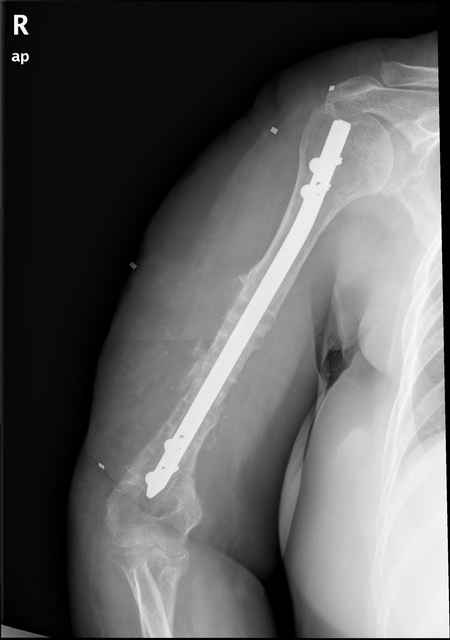

Больная 48 лет, медсестра. Травма получена 7 лет назад, оперирована первично в Турции -

остеосинтез пластиной - несращение - реостеосинтез стержнем там же через год (обычным, с

выстоянеием его в полость плеча) - несращение - поступила к нам впервые в марте 2008 года -

удаление стержня, реостеосинтез пластной и костная пластика, в течение 2 лет лизис кости

вокруг винтов, смещение фиксатора, в марте 2010 - удаление пластины, реостеосинтез

интрамедуллярным стержнем с блокированием (рассверливание + костная пластика).

В динамике - вновь лизис в области перелома, нестабильность дистальных блокирующих винтов.